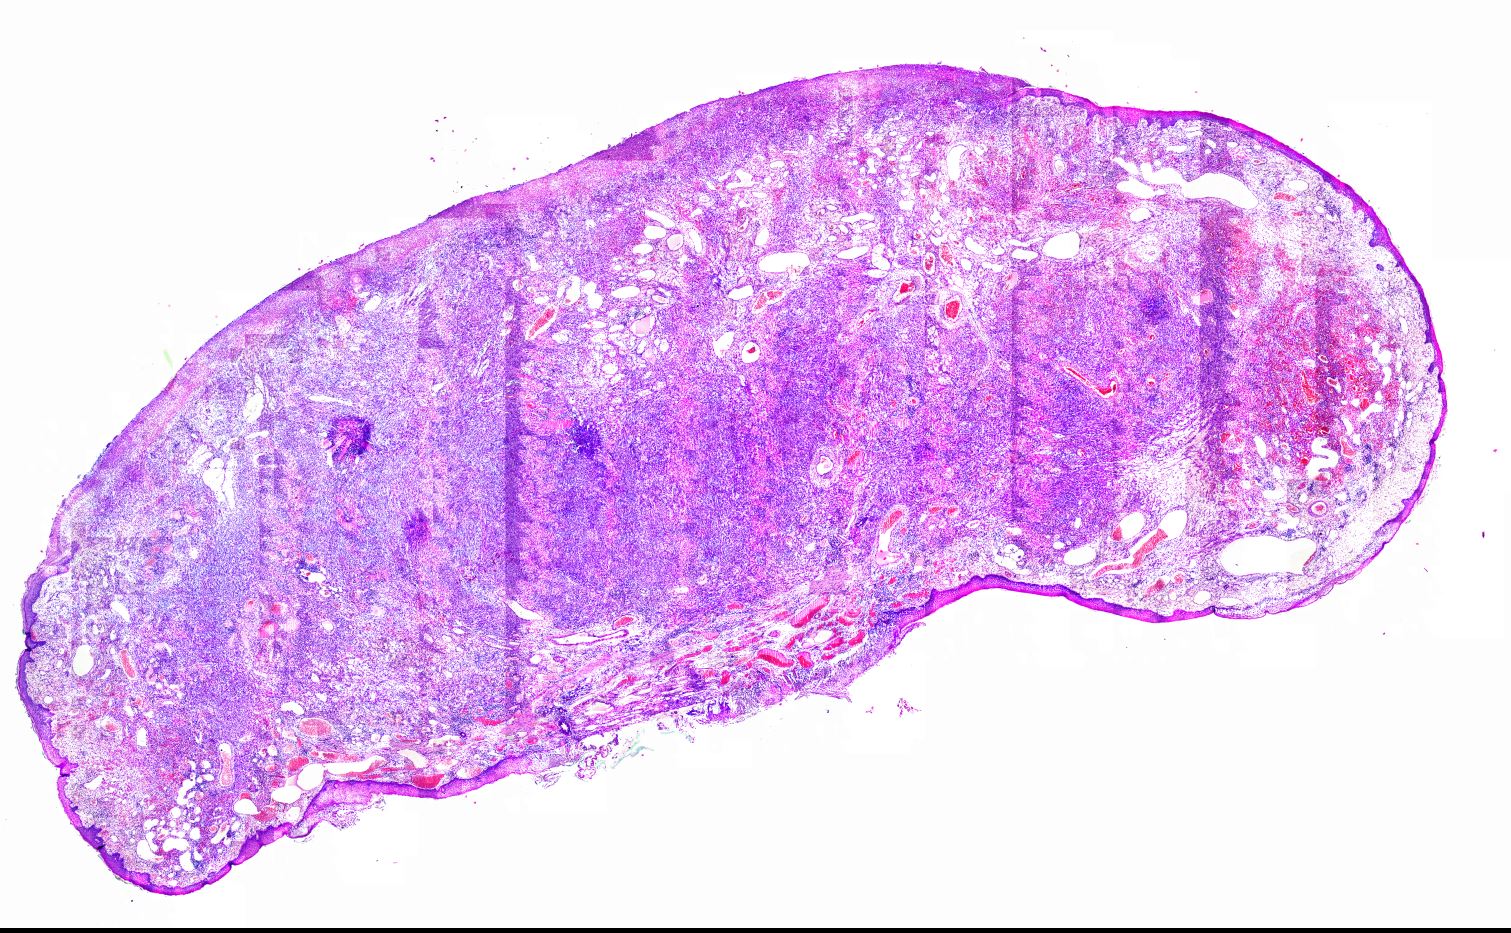

Diffuse sclerosing papillary thyroid carcinoma DSV-PTC typically presents with diffuse thyroid involvement affecting both lobes, marked stromal fibrosis, squamous metaplasia, numerous psammoma bodies, lymphocytic infiltration